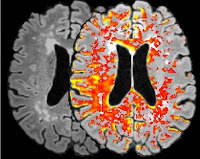

Figure 1 : Barrière Hémato-Encéphalique

Une analyse tissulaire post-mortem ainsi qu’une imagerie obtenue par résonance magnétique nucléaire a permis de quantifier la perméabilité de la BHE dans le cerveau humain. Une étude portant sur des sujets âgés de 21 à 83 ans a mis en évidence une augmentation linéaire de la perméabilité de la BHE en fonction de l’âge, à 60 ans presque la moitié de la population étant affectée par une rupture de la BHE (7). (Figure 2)*

*Figure 2: MRI-scan images of the blood-brain-barrier leakage. Maastricht University, News & Events, 1st of June 2016